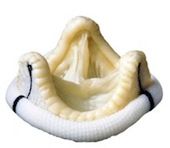

دریچه بیولوژیکی از کیسه قلب گاو

دریچه بیولوژیکی از کیسه قلب گاو

دریچه بیولوژیکی خوکی

دریچه بیولوژیکی خوکی

حلقه جهت ترمیم دریچه

حلقه جهت ترمیم دریچه